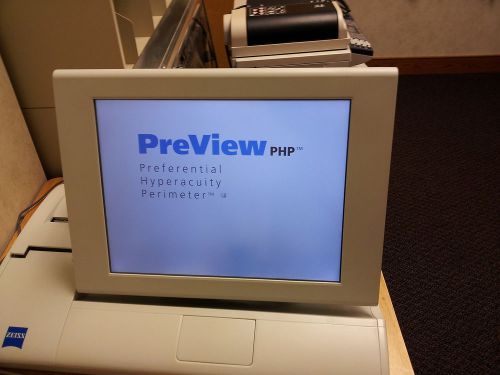

ZEISS PREVIEW PHP - PREFERENTIAL HYPERACUITY PERIMETRY